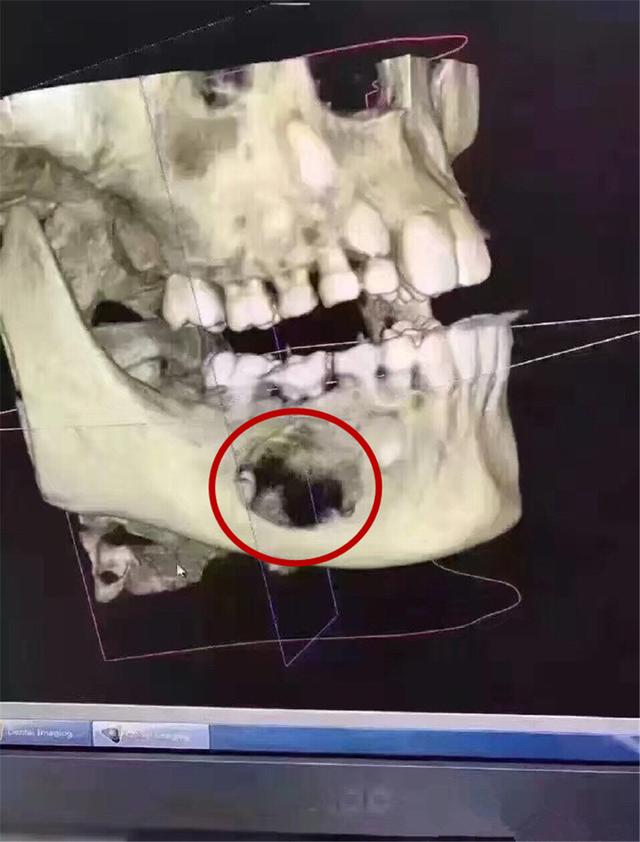

這是一位9歲的孩子,因為(wei) 沒有重視乳牙護理和齲齒治療,導致乳牙下麵的頜骨大麵積吸收的**。